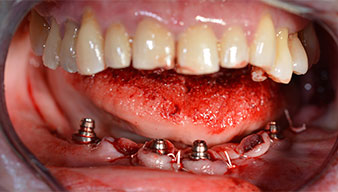

L’extraction de la denture résiduelle à la mandibule a exposé la crête alvéolaire de 37 à 47.

Le trou mentonnier doit d'abord être identifié comme une structure anatomique limitante, puis l'os cortical de la crête a été régularisé avec une pièce à main droite et une fraise sphérique de grande taille (Fig. 4).